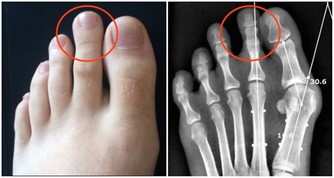

從解剖學角度來分析,膝關節的周圍肌肉薄弱,上下骨骼形成的槓桿長,承受了人體86%的重量,所以膝關節在運動中最易受傷。

有一個數據:走路時髖關節、膝蓋等承受重量約是體重的1.6倍,快走是3.6倍,跑步則是5倍。

以一個體重60公斤的人為例,平路行走時兩邊膝蓋各承重60公斤,但爬樓梯或爬山時膝蓋負重竟變成高達240公斤。

上山時膝關節負重等於自身體重,而下山時除了自身體重以外,還要負擔下沖的力量,這樣的衝擊會加大對膝關節的磨損。

▲爬樓梯時,腰部以下的關節都要承受運動者自身的體重,其中以膝蓋受力最多,為平時的4倍左右。